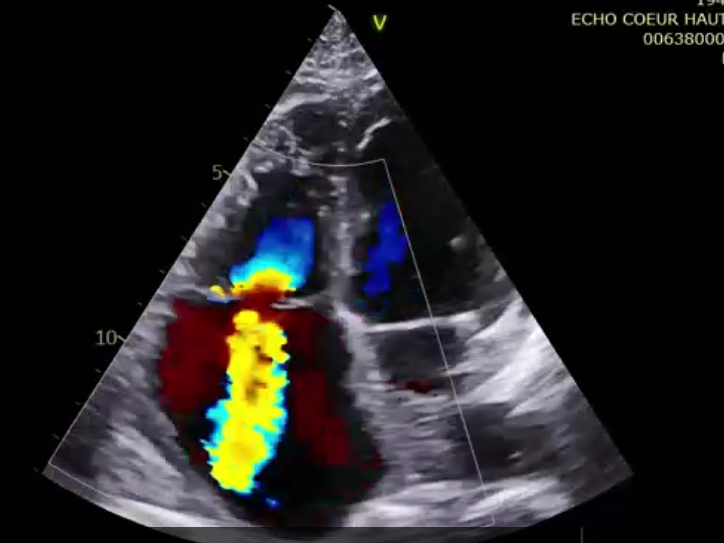

術前超聲提示大量三尖瓣反流

第二名患者是一位79歲的女性,術前TTE診斷TR等級4+,既往有高血壓、腎功能不全、肺動脈高壓的病史。術者在擁有第一臺手術的經驗后,在TEE和DSA的引導下非常順利地完成瓣膜的釋放,術后瓣膜形態穩定,TEE提示即刻反流0+。患者術后七天TTE復查提示無明顯三尖瓣反流,瓣膜整體形態非常穩定。